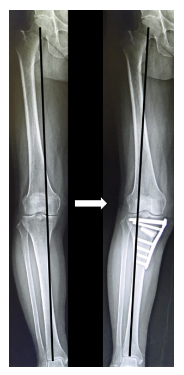

関節リウマチや変形性膝関節症によって軟骨がすり減り、鎮痛薬や関節注射などの保存療法を受けても膝の痛みが緩和されない患者様には人工関節置換術を数多く実施しています。また人工関節置換術だけではなく、ご自身の膝関節温存を希望される患者様には膝周囲骨切り術も積極的に行っています。ただしどちらの手術も長所と短所がありますので、主治医とよく相談して治療法を選択することをお勧めします。

人工膝関節置換術前と術後のレントゲン写真

高位脛骨骨切り術前と術後のレントゲン写真